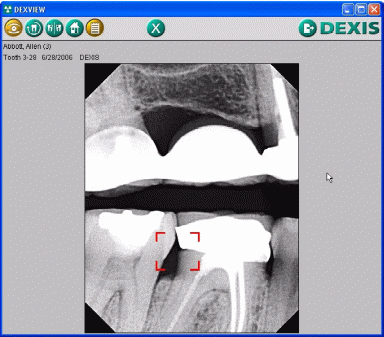

После получения доступа к системе врачи могут просматривать снимки своих пациентов, используя полосу прокрутки слева или введя данные пациента в строку поиска (рис.3.29). После выбора пациента происходит загрузка его данных с сервера и открывается снимок (рис.3.30). Если открытие снимка не происходит, значит у врача нет доступа к данному снимку и его расшифровка при загрузке с сервера не произошла.

Рисунок 3.30 Рентгеновский снимок пациента